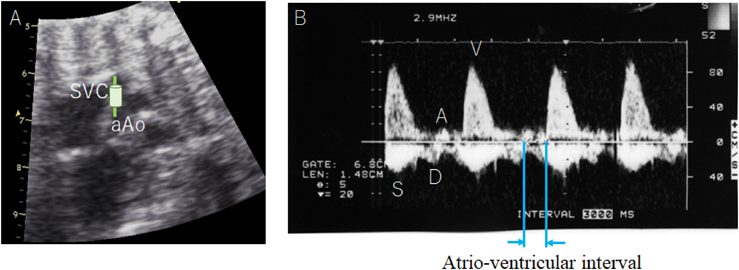

| Fetal hydrops |

| Cardiac function, such as atrio-ventricular valve insufficiency or cardiomegaly |

| Treatment (after arrhythmia is diagnosed and comprehensively evaluated) |

|---|

| Antiarrhythmic drugs: digoxin, flecainide, sotalol, amiodarone, magnesium sulfate, lidocaine, propranolol, or mexiletine |